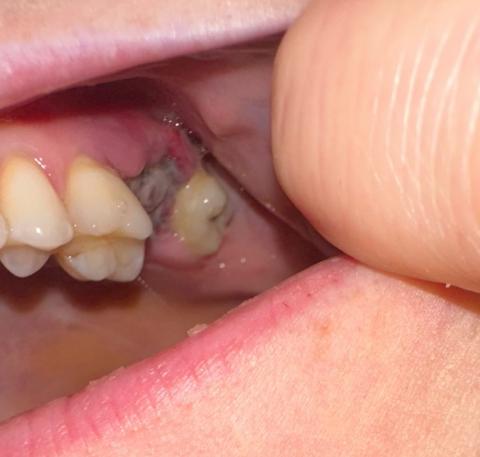

Acute Infection and Necrotic Tissue Formation on Posterior Molar – Early Signs of Spreading Dental Abscess

Upon zooming in at 100%, the molar region (likely third molar or second molar area) shows grayish-black necrotic tissue, possibly indicating infection or tissue death. There is yellowish exudate or pus, a clear sign of acute infection. The gum tissue around the infected site appears inflamed. The adjacent tooth structure is partially covered by infected tissue with visible gum swelling. This can be a sign of pericoronitis, abscess, or developing dry socket (if post-extraction).

This case suggests one of the following:

Acute pericoronitis (infection of the gum flap covering a partially erupted molar)

Early abscess formation due to bacterial spread

Necrotic socket infection if the tooth was recently extracted